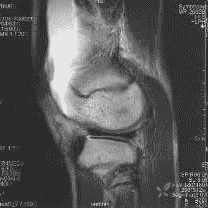

膝关节(knee joint)由股骨内、外侧髁,髌骨和胫骨内、外侧髁组成。是全身结构最复杂的关节。

点击可查看清晰大图